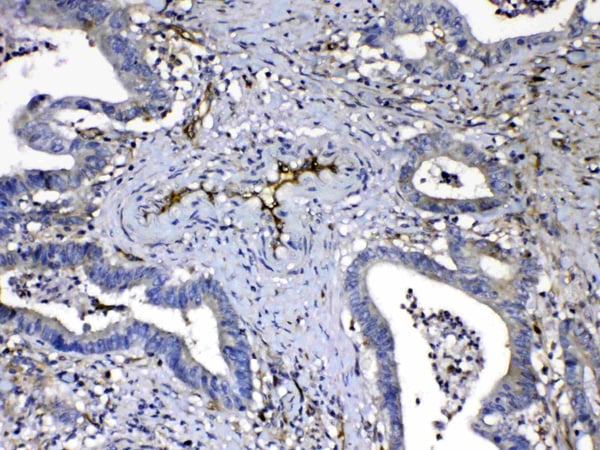

IHC (Immunohiostchemistry)

(Figure 2. IHC analysis of HOMER3 using anti-HOMER3 antibody (AAA124742).HOMER3 was detected in paraffin-embedded section of human intestinal cancer tissue. Heat mediated antigen retrieval was performed in citrate buffer (pH6, epitope retrieval solution) for 20 mins. The tissue section was blocked with 10% goat serum. The tissue section was then incubated with 1ug/ml rabbit anti-HOMER3 Antibody (AAA124742) overnight at 4 degree C. Biotinylated goat anti-rabbit IgG was used as secondary antibody and incubated for 30 minutes at 37 degree C. The tissue section was developed using Strepavidin-Biotin-Complex (SABC) with DAB as the chromogen.)